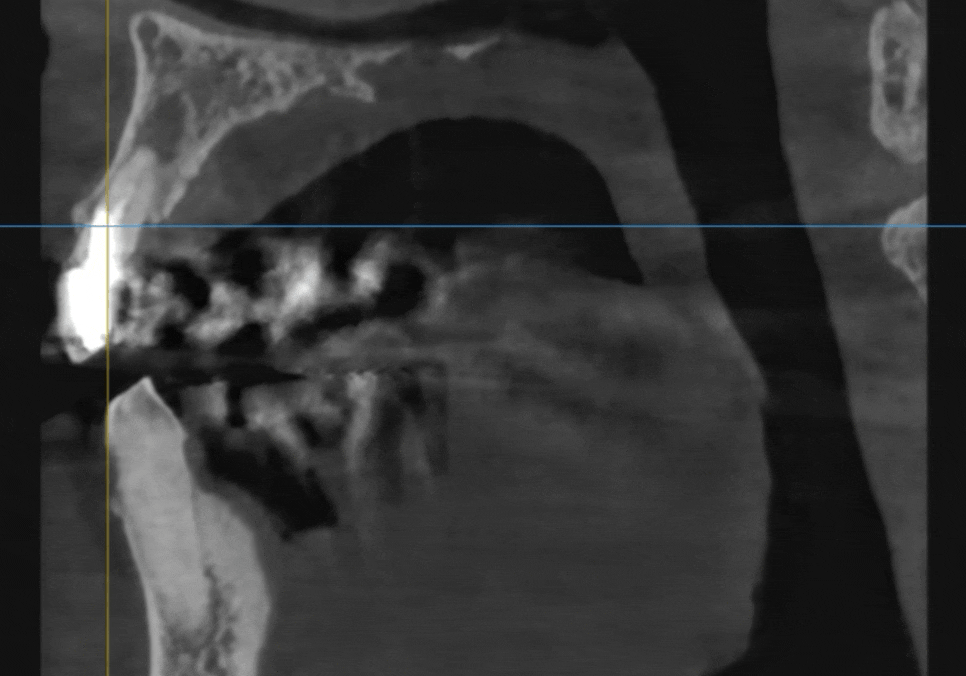

내비게이션 임플란트가 더 안전한 이유

출혈에 예민한 분들일수록

저희는 내비게이션 임플란트를

적극적으로 활용합니다.

수술 전에 3D 데이터를 바탕으로

컴퓨터상에서 가상 수술을 먼저 진행해요.

위험한 신경이나 혈관 위치를

미리 파악하고 피할 수 있어 훨씬 안전합니다.

정확한 길을 미리 알고 있기 때문에

잇몸을 넓게 열지 않습니다.

작은 구멍만 내어 심을 수 있어 출혈이 적고,

당연히 수술 후 붓기나 통증도

눈에 띄게 줄어들게 됩니다.